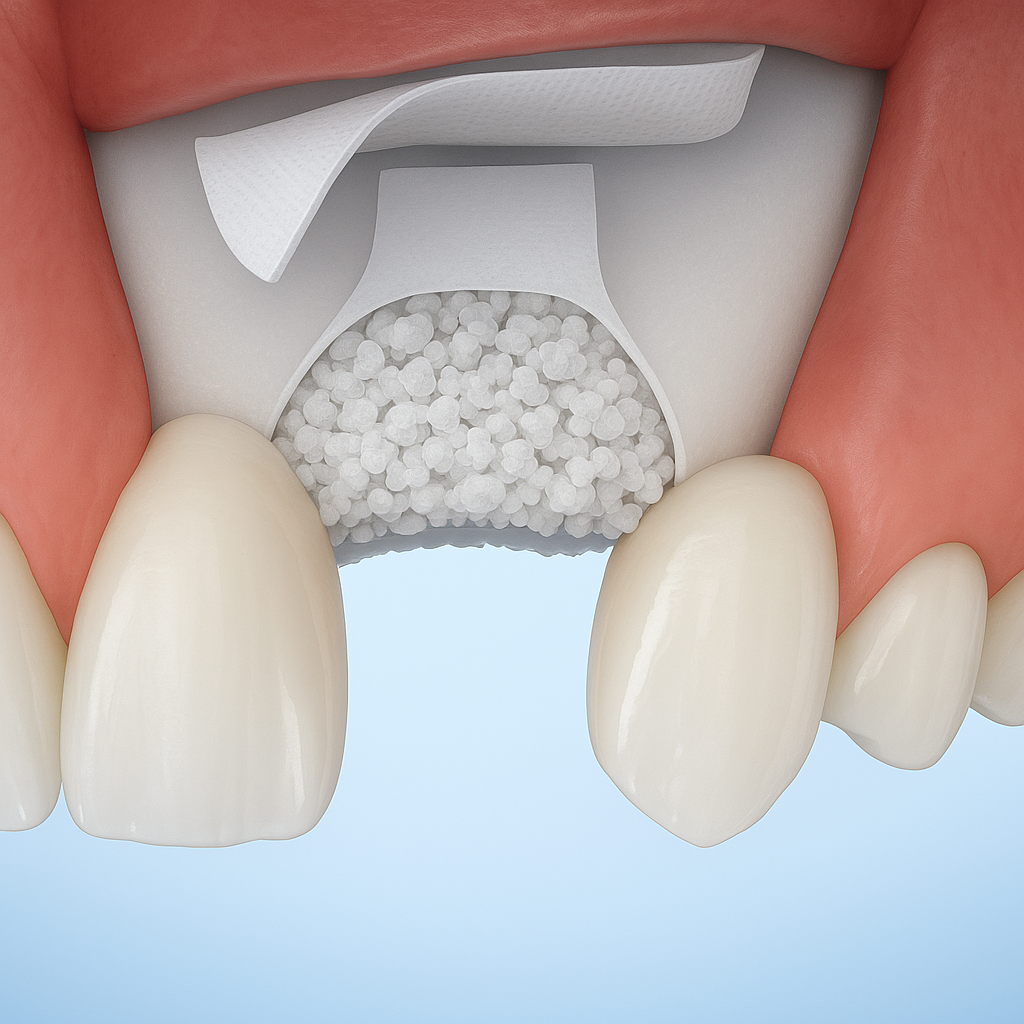

Injerto de Hueso

El injerto de hueso es clave para regenerar tejido óseo perdido y crear una base sólida para tratamientos como implantes dentales, para ello, se utilizan materiales biocompatibles y técnicas avanzadas.

¿De dónde se obtiene el hueso para el injerto?

Puede provenir de tu propio cuerpo (autoinjerto), de un banco de huesos (aloinjerto), de materiales sintéticos o incluso hueso animal procesado (xenoinjerto).

¿Es seguro realizarse un injerto de hueso?

Sí, cuando lo realiza un profesional capacitado. Los materiales utilizados están esterilizados y son biocompatibles.